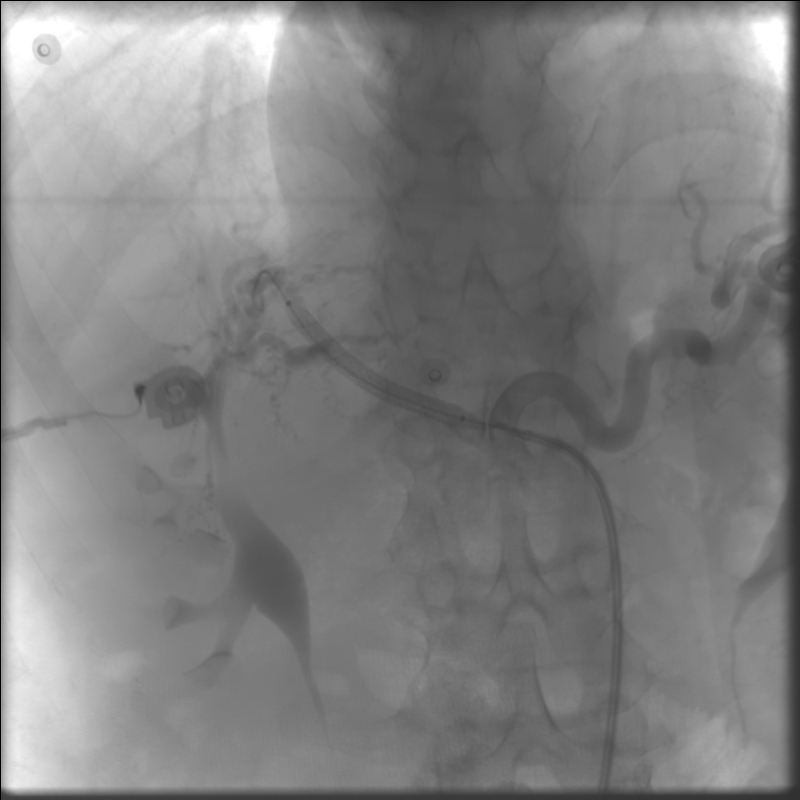

Рентгенэндоваскулярные вмешательства

эндопротезирование печеночной артерии